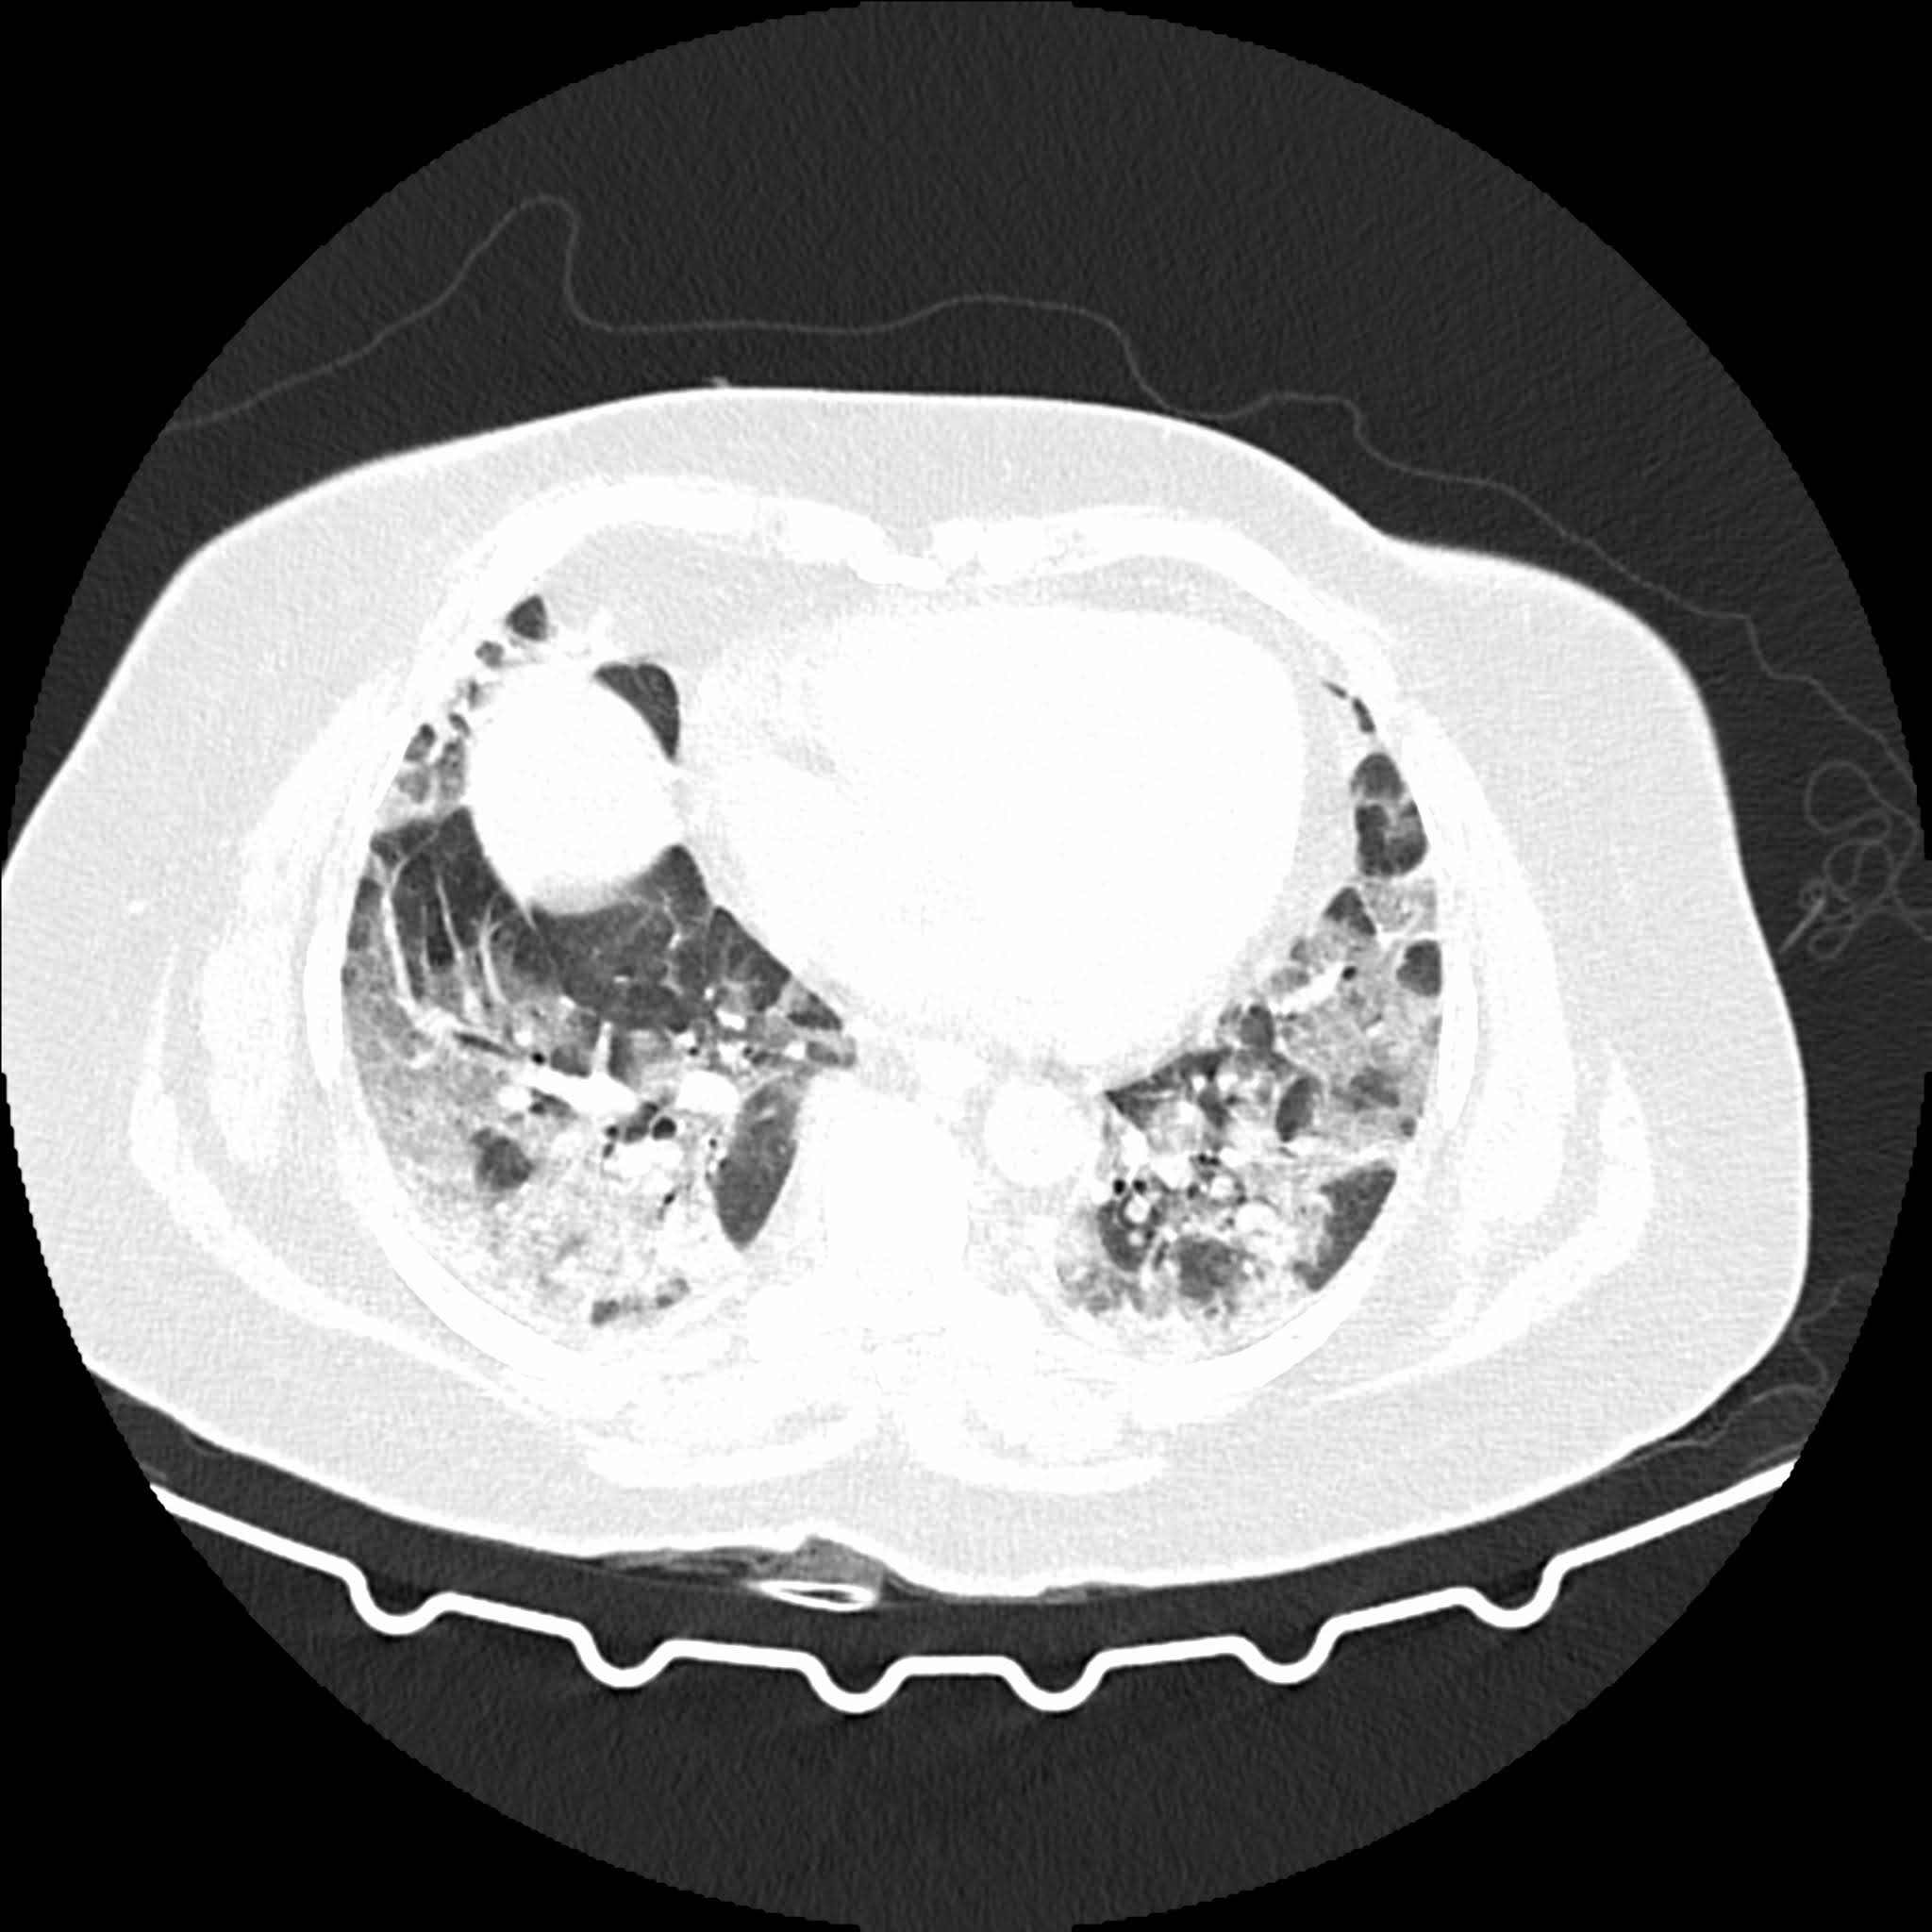

HRCT THORAX

There  are extensive bilateral patchy ground glass opacities with mild consolidations seen in all the Jones of both the lungs